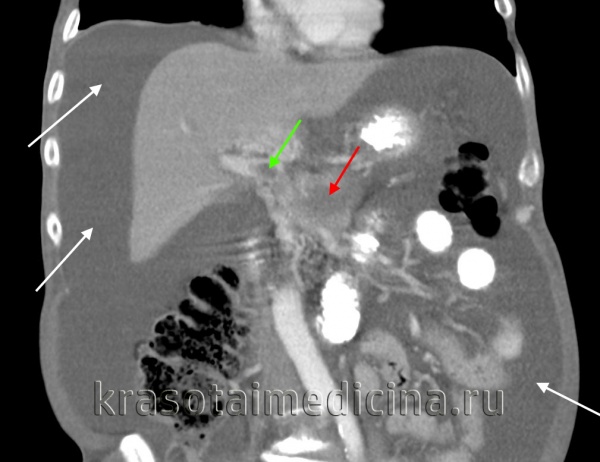

КТ ОБП. Портальная гипертензия на фоне обструкции воротной вены опухолью поджелудочной железы (красная стрелка). Опухолевый тромб (зеленая стрелка) в воротной вене. Асцит (белая стрелка).

Патогенез

Основными патогенетическими механизмами портальной гипертензии выступают наличие препятствия для оттока портальной крови, увеличение объема портального кровотока, повышенное сопротивление ветвей воротной и печеночных вен, отток портальной крови через систему коллатералей (потртокавальных анастомозов) в центральные вены.